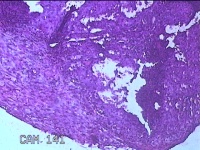

右卵巢黄体囊肿

性别

女

年龄

41岁

临床诊断

右卵巢黄体囊肿破裂

一般病史

下腹痛3小时。

标本名称

大体所见

灰白暗红色囊性肿物2x0.8x0.7cm一个,表面糜烂,切开肿物,内见大量凝血块,囊壁厚约0.1cm。